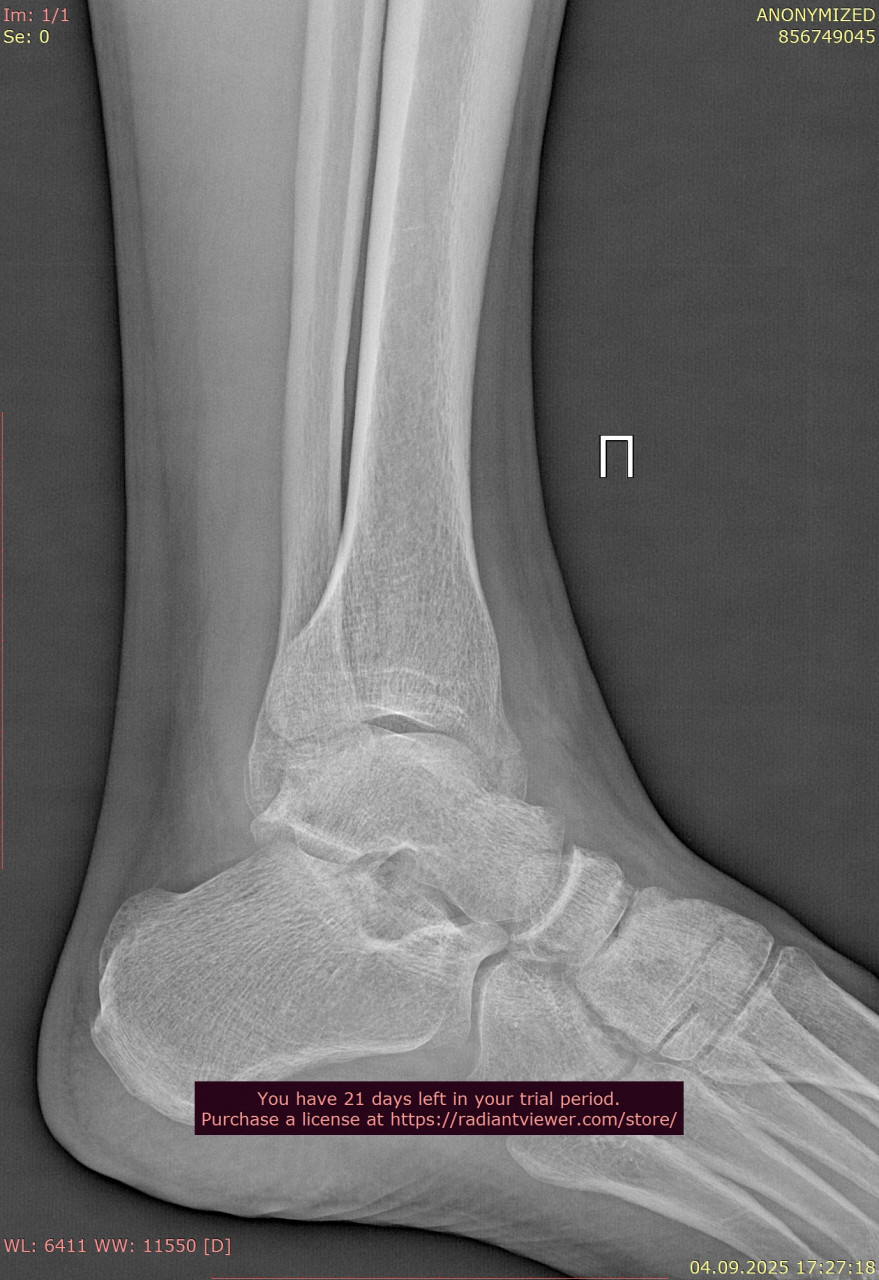

Посмотрите, пожалуйста, еще снимки голеностопного сустава от 23.06.2025, когда был перелом, и спустя почти 11 недель от 04.09.2025. Нормально ли сросся перелом, нужны ли еще снимки?

Здравствуйте. Судя по срокам и динамике на снимках, перелом срастается удовлетворительно, костная мозоль сформирована и переходить к постепенной нагрузке можно, но окончательное решение и необходимость повторного рентгена определяет ваш лечащий травматолог с учётом клиники и остеопении.